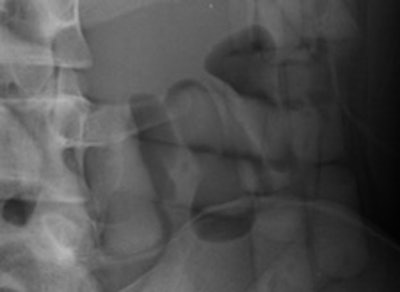

Top left: Low-dose linear slit digital radiography (LSDR) of a typical body packer with 145 intracorporal packs along the alimentary tract. Bottom left: Magnified view of the packs. Note the radiolucent rim within the periphery of the packs due to air trapping creating the so-called "double-condom sign" and "halo sign." Top right: DR of a typical body packer with 83 cocaine packs in the gastrointestinal tract. Bottom right: Note the longitudinal packs (weight approximately 10 to 12 g) projecting over the colon. The magnified view depicts the typical "double-condom sign" due to inevitable air trapped within the wrapping layers during manufacture.DR and low-dose linear slit digital radiography exams were less accurate. CT exams had an overall accuracy rate of 97.1%, followed by DR (71.4%, and 60% for low-dose linear slit digital radiography).